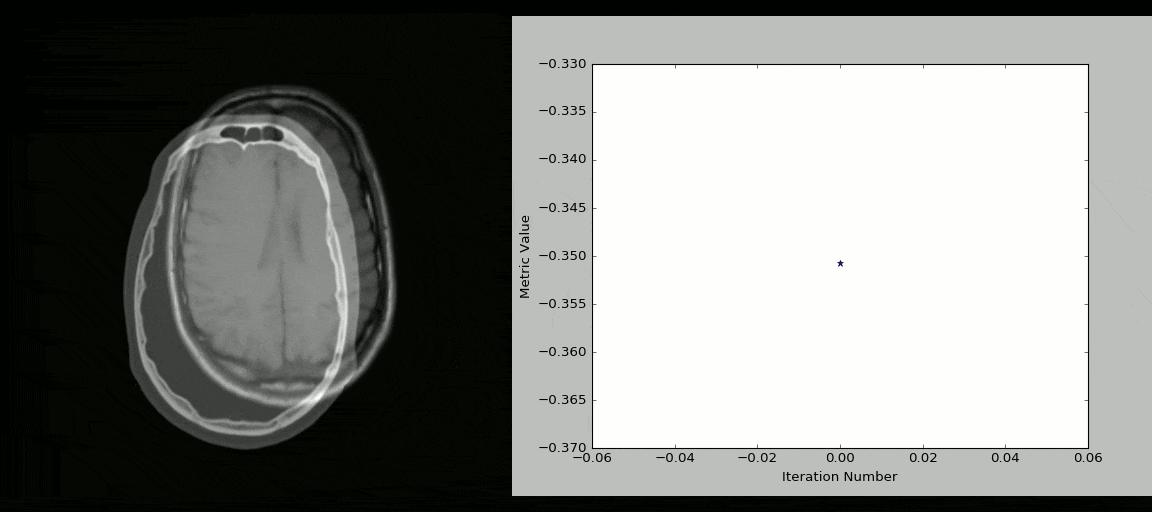

8、SimpleITK

ITK(Insight Segmentation and Registration Toolkit)是一个为开发者提供普适性图像分析功能的开源、跨平台工具套件,SimpleITK 则是基于 ITK 构建出来的一个简化层,旨在促进 ITK 在快速原型设计、教育、解释语言中的应用。SimpleITK 作为一个图像分析工具包,它也带有大量的组件,可以支持常规的滤波、图像分割、 图像配准 功能。尽管 SimpleITK 使用 C++ 编写,但它也支持包括 Python 在内的大部分编程语言。

有很多 Jupyter Notebooks 用例可以展示 SimpleITK 在教育和科研领域中的应用,通过这些用例可以看到如何使用 Python 和 R 利用 SimpleITK 来实现交互式图像分析。

示例

使用 Python + SimpleITK 实现的 CT/MR 图像配准过程: